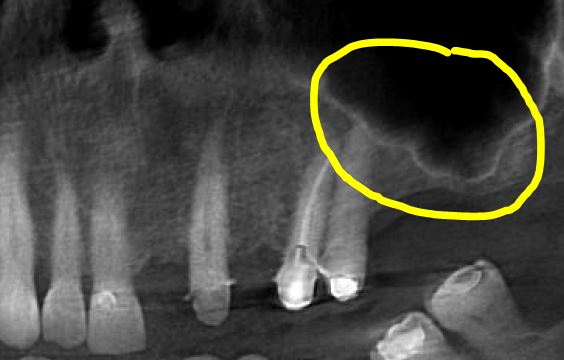

הרמת סינוס

הסינוסים הם חללים משני צידי האף. עם השנים, הסינוסים הולכים וגדלים על חשבון העצם של הלסת העליונה. תהליך זה מואץ לאחר אובדן שיניים טוחנות בלסת העליונה. כאשר רוצים למקם שתלים דנטלים, יש צורך בנפח עצם מספק סביב השתלים על מנת לאפשר את קליטתם. הרמת סינוס היא אמצעי יעיל להחזרת המצב לקדמותו וקבלת נפח עצם מספק.

ישנם שני סוגים של הרמת סינוס:

סגורה - במצבים בהם חסר העצם מינימלי, ניתן לבצע פעולה פשוטה יחסית בזמן מיקום השתלים הדנטלים.

פתוחה - כאשר חסרה יותר עצם, מבוצעת פעולה זו המאפשרת הגדלת נפח העצם בצורה משמעותית. פעולה זו מבוצעת בנפרד או ביחד עם מיקום השתלים, כתלות בחומרת אובדן העצם במקום.

במרפאתנו הרמות הסינוס מבוצעות על ידי מומחה לכירורגיה פה ולסת.